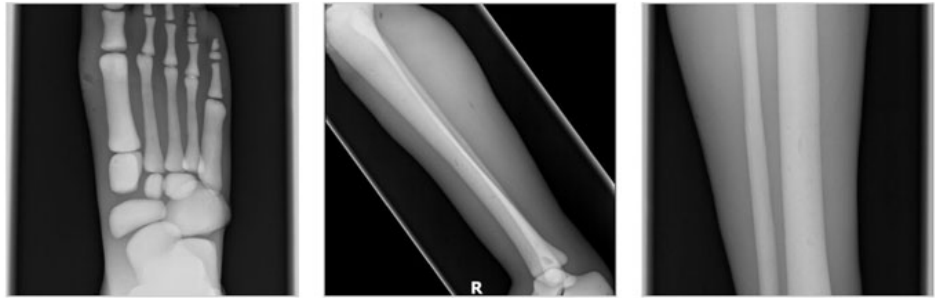

成人腿部模體,用于 X 射線 CT 和超聲波的成人腿部(肌肉)模型是一種基于人類男性腿部平均解剖結(jié)構(gòu)設(shè)計(jì)的逼真模型。它具有所有基本的骨骼和

軟組織特征,使其成為學(xué)習(xí)、研究和測(cè)試醫(yī)學(xué)成像設(shè)備的理想工具。 模體可用于研究不同方向和定位技術(shù)的多種診斷性 X 射線 CT 和超聲程序。根據(jù)

要求,該產(chǎn)品可以根據(jù)不同的病理進(jìn)行定制,也可以用于特定的培訓(xùn)應(yīng)用。 模體尺寸:965.2 x 254 x 177.8 毫米,重量:12kg(約)